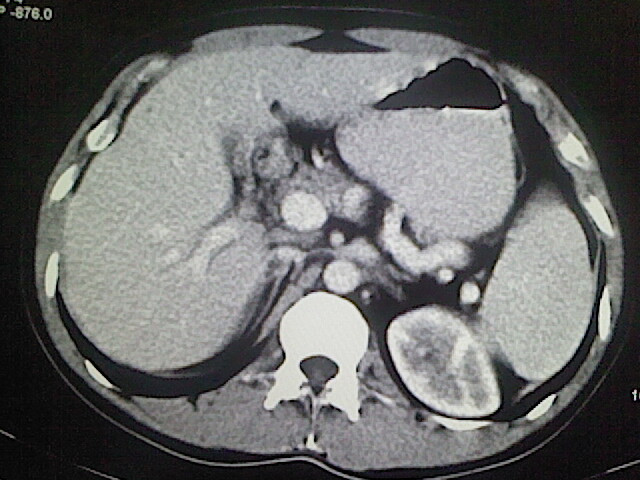

以下是引用卜一在2009-3-14 9:49:00的发言:[br]胆囊萎缩,胆囊壁不规则增厚,内部结构模糊,增强明显强化。另:肝左叶外侧段肝囊肿。支持:慢性胆囊炎!高度可疑:胆囊癌!

以下是引用余辉在2009-3-14 8:48:00的发言:[br]1)慢性胆囊炎。2)肝左叶外侧段肝囊肿。3)脂肪肝。[br]支持,胆囊萎缩,密度增高,不知b超具体有何提示,钙胆汁?结石?

以下是引用jiangjing在2009-3-14 10:18:00的发言:[br]1)慢性胆囊炎。2)肝左叶外侧段肝囊肿。3)脂肪肝。4.】建议行肝功能检查